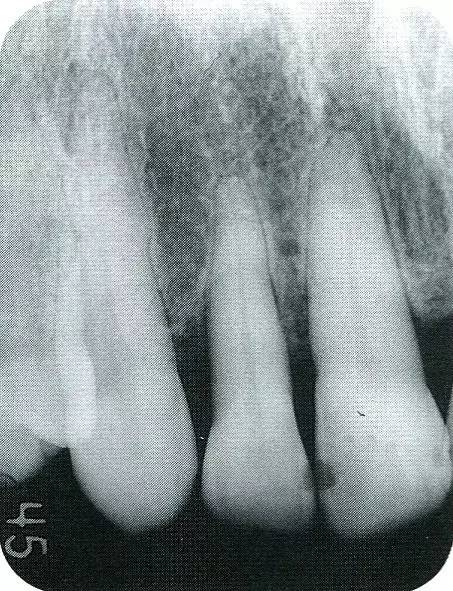

▲圖9-2  術(shù)前x片。

▲圖9-4  術(shù)前的x片。